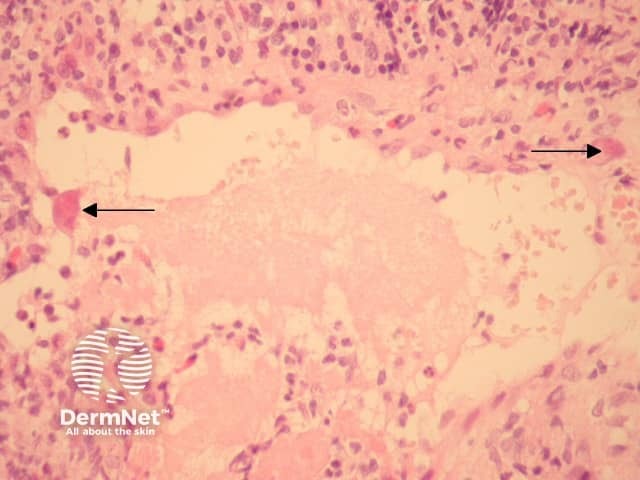

Cytomegalovirus (CMV) is a member of the family Herpesviridae. In cutaneous cytomegalovirus infection, markedly enlarged endothelial cells are seen lining small vessels (Figure 1, arrows). These are larger and eosinophilic when compared with normal or reactive endothelial cells. The hallmark histologic feature is a large intranuclear inclusion which is densely eosinophilic (Figure 2, arrow). Other cells such as fibroblasts and epithelial cells are less commonly involved.

The inclusions may be seen in the context of overlying epidermal ulceration and other non-specific inflammatory changes. Leukocytoclastic vasculitis is a described reaction pattern.

Figure 2